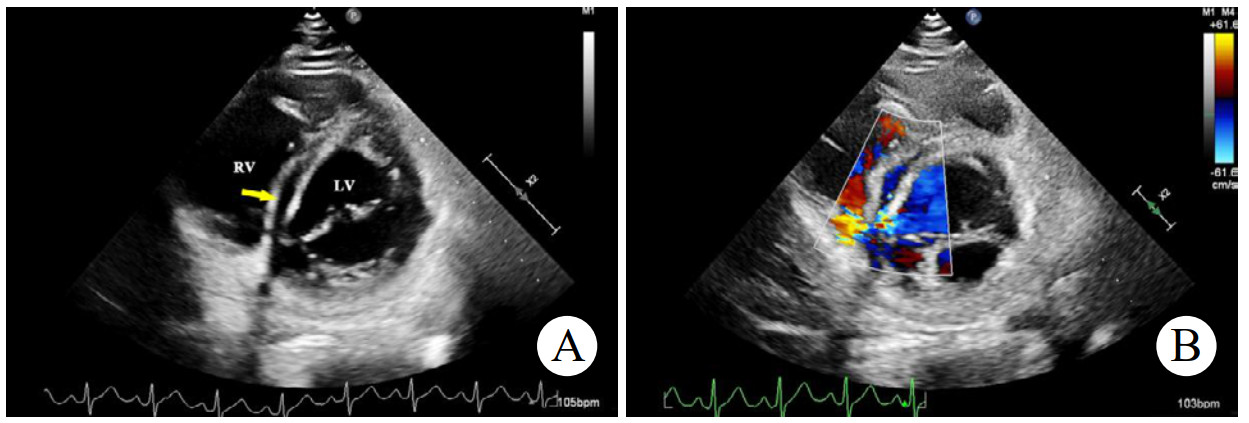

辅助检查如下。实验室检查:高敏C反应蛋白(hs-CRP)和红细胞沉降率(erythrocyte sedimentation rate, ESR)轻度升高。心电图:正常窦性心律,无ST段异常改变。胸部CT:双侧肺门中心对称分布的斑片状高密度影,部分实变,伴空气支气管征,病变边缘模糊。超声心动图:二维超声(2D)主动脉短轴切面显示右乏氏窦瘤破裂(ruptured of ASV, RASV),破入右心房形成“囊袋状”结构,长约1.7 cm,基底部破口内径约0.8 cm(图 1A)。彩色多普勒(color Doppler flow imaging, CDFI)显示全心动周期的左向右分流(图 1B)。连续多普勒(continuous doppler, CW)测得连续分流。室间隔内见4.0 cm×0.7 cm无回声区(图 2A),CDFI显示彩色血流信号随心动周期进出该无回声区(图 2B),考虑室间隔夹层瘤(dissecting aneurysm of the interventricular septum, DAIS)。实时双平面成像同步显示窦瘤破口与室间隔夹层相延续。应用Philips TrueVue三维(three-dimensional, 3D)超声心动图成像模式直观展示室间隔夹层瘤的立体结构(图 3)。

| 注:A为2D超声显示室间隔内无回声区(黄色箭头);B为CDFI显示彩色血流信号进出室间隔无回声区 图 2 2D及CDFI显示左室短轴二尖瓣水平切面室间隔夹层动脉瘤 |